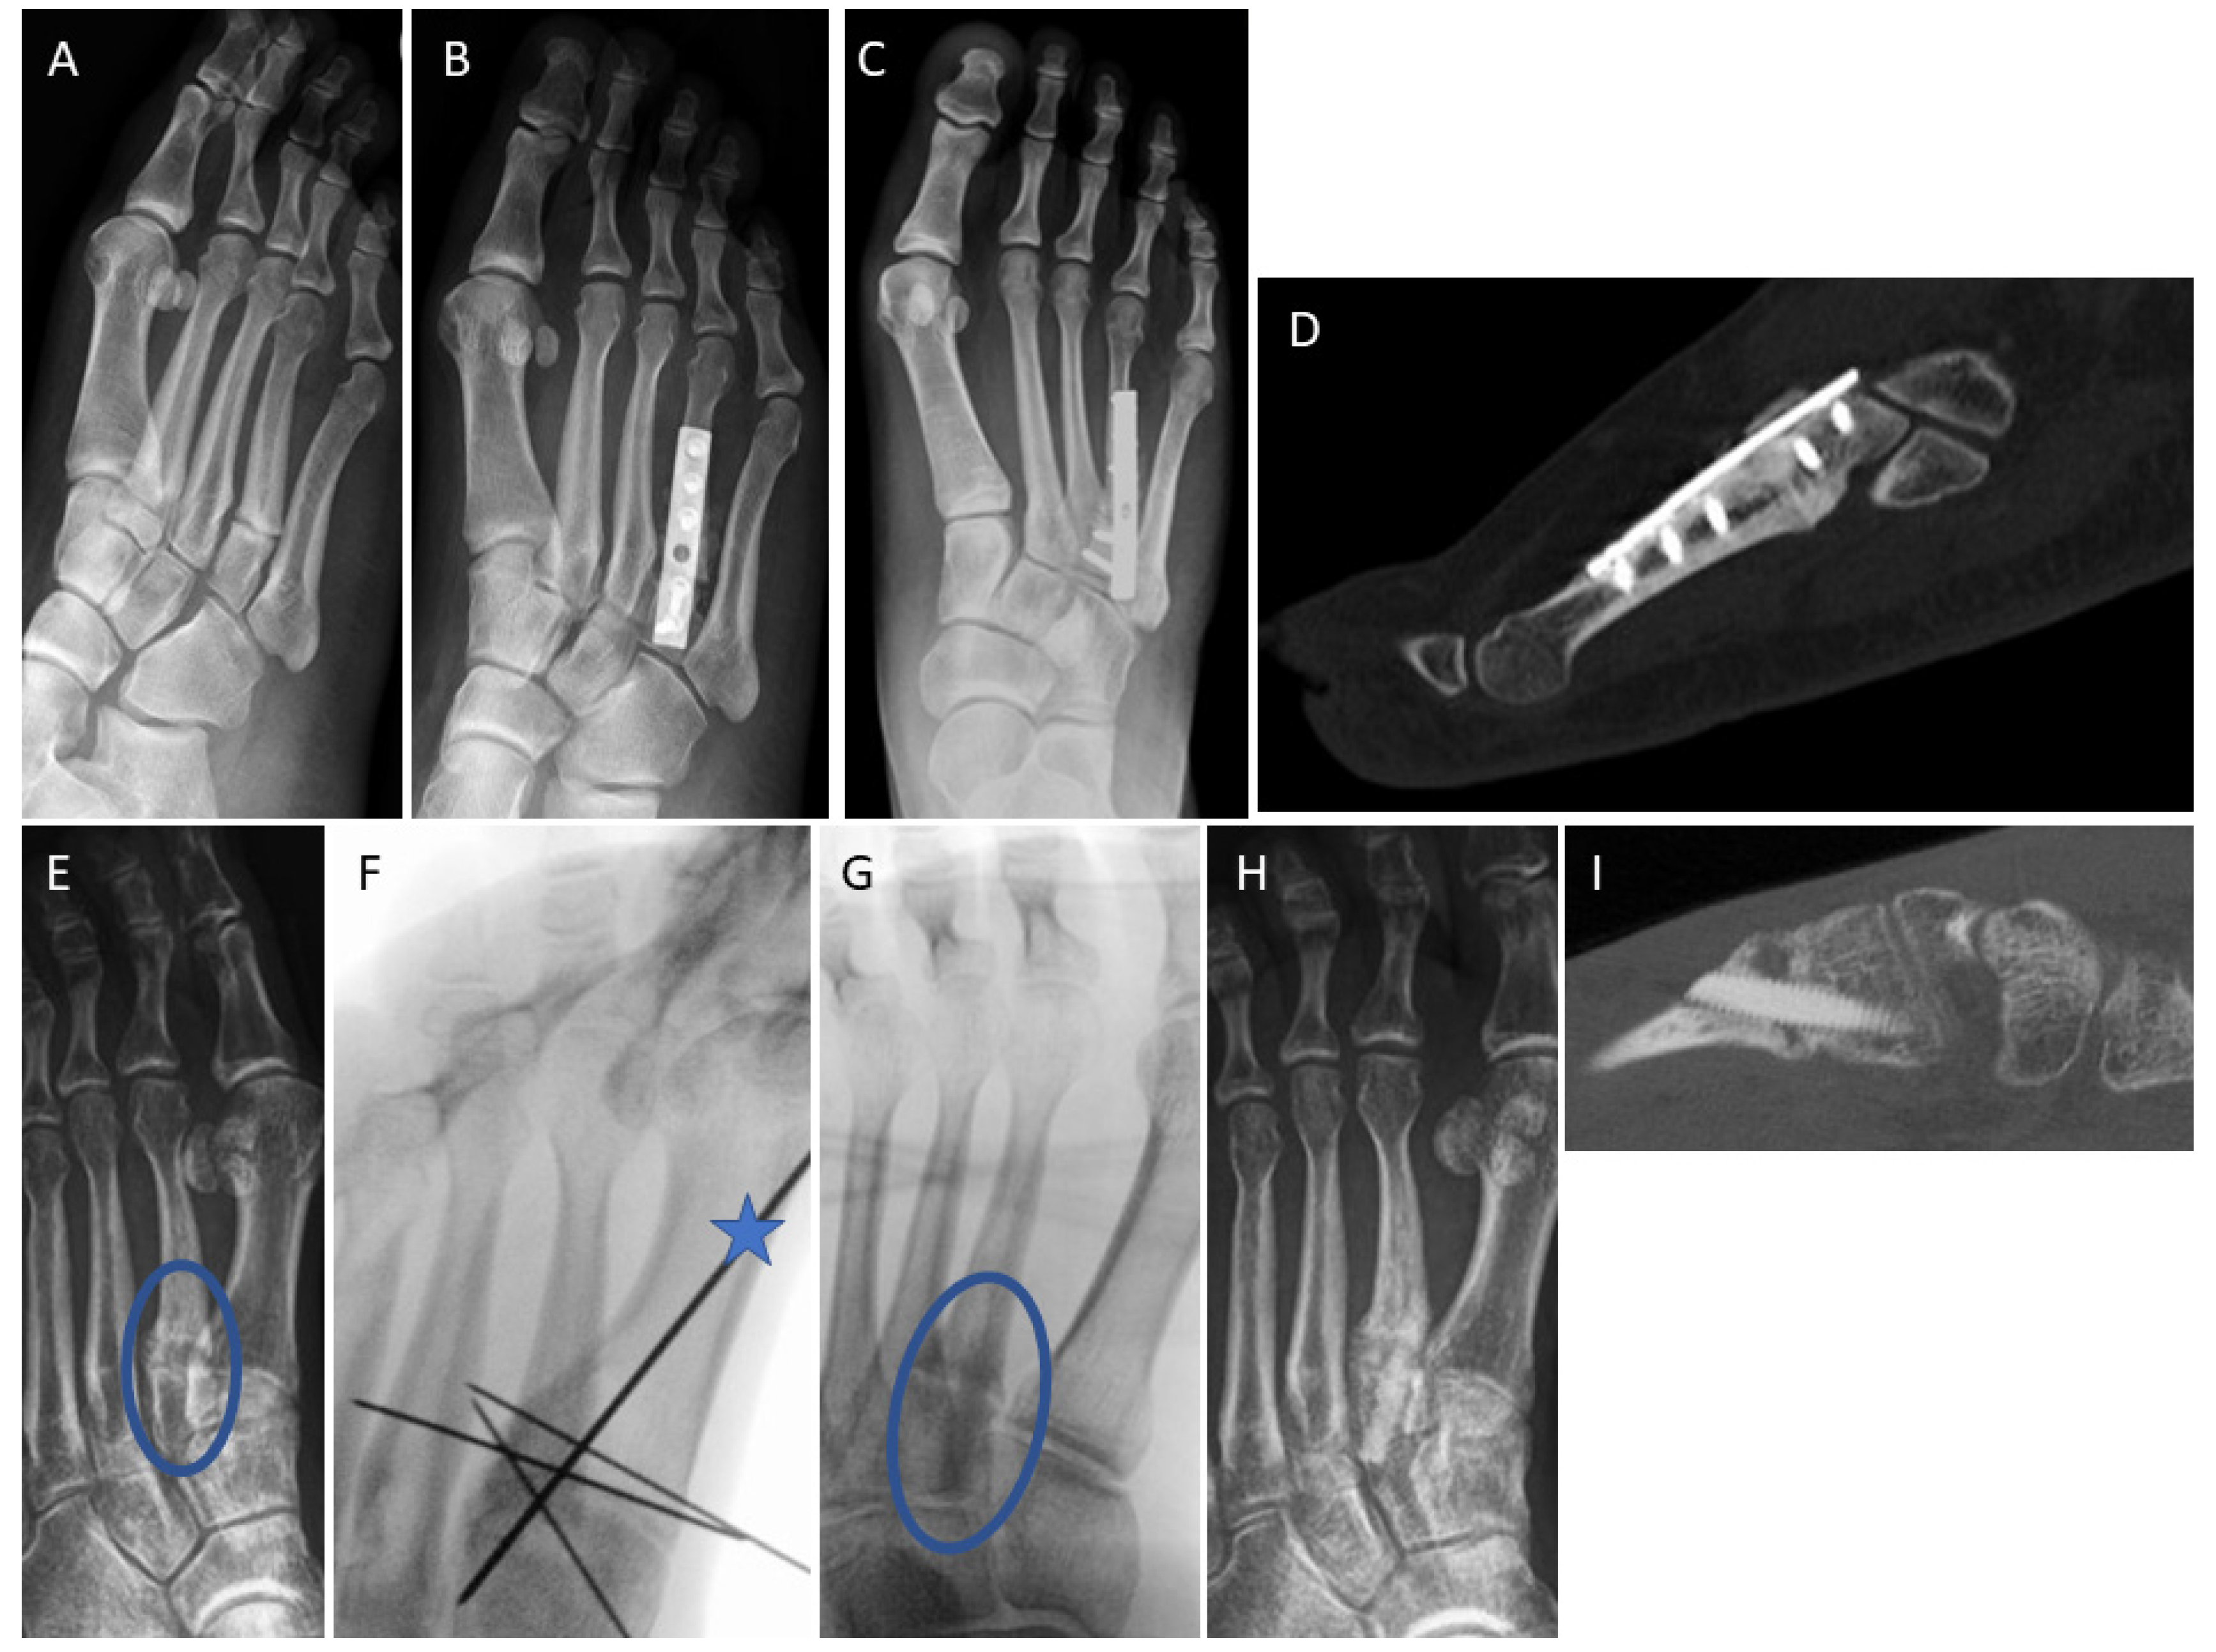

3.4. Examples for Bone Healing

3.5. Clinical Complications

3.6. Radiological Findings of Interest